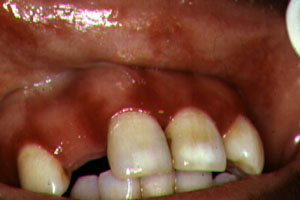

La

periodontitis ulceronecrotizante se manifiesta en menos

del 5% de los casos con pérdida de hueso y tejido blando en los

pacientes VIH con recuento de CD4 inferior a 200 y puede progresar a

estomatitis ulceronecrotizante Se encuentran microorganismos usuales

de la boca y organismos ocasionalmente atípicos como

pseudomonas, se han aislado bacilos entéricos y bacterias que no

pertenecen a la flora oral..